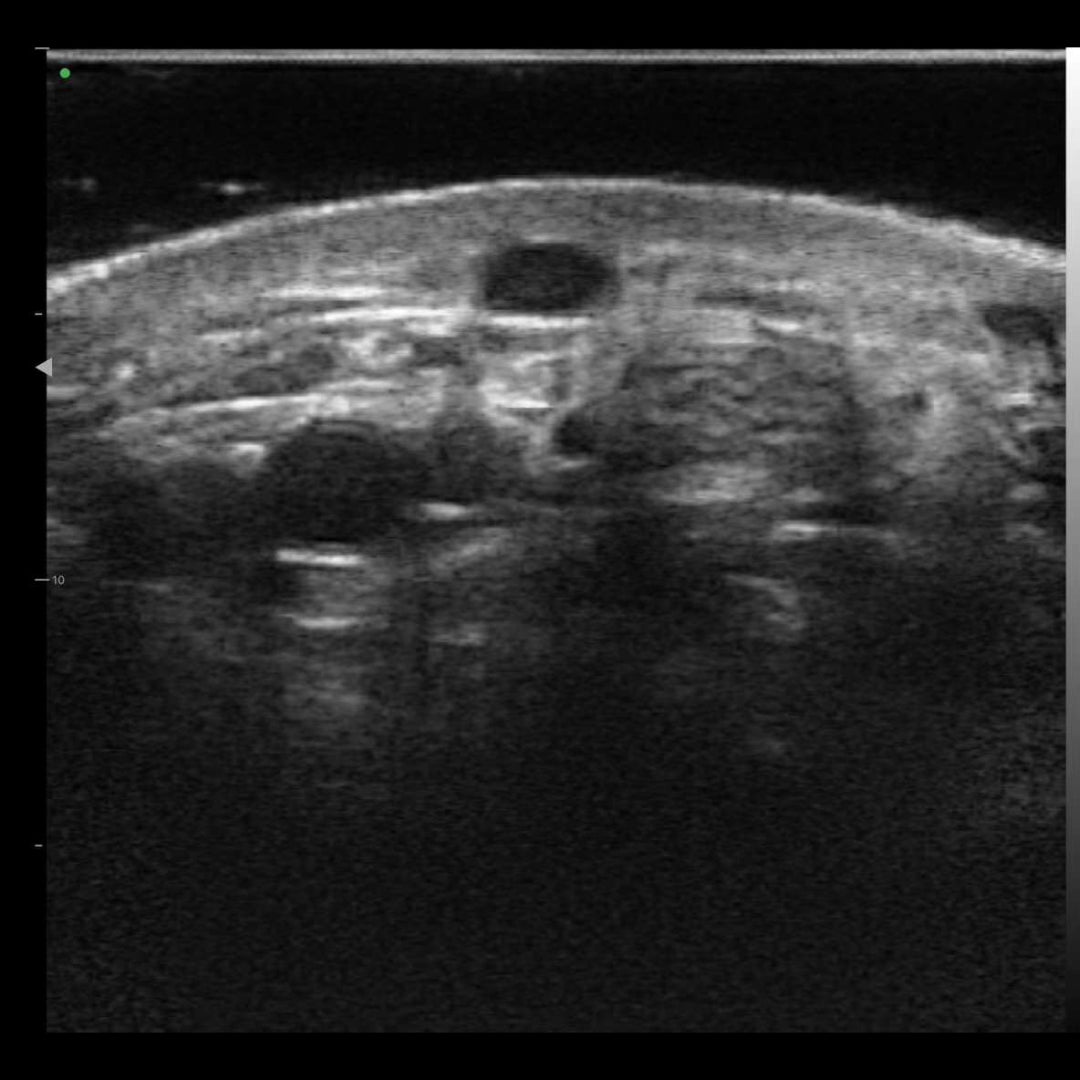

Imágenes de la vida real

Nuestros dispositivos reproducen una excelente calidad de imagen.

Diseñado con una plataforma innovadora de integración y procesamiento de datos, nuestro Transductor Lineal de Ultra Alta Definición HM20L visualiza claramente en tiempo real los vasos faciales, nervios, capas cutáneas y subcutáneas de las redes neurovasculares faciales para guiar de manera segura los procedimientos. Esto elimina riesgos y garantiza la seguridad de los pacientes.